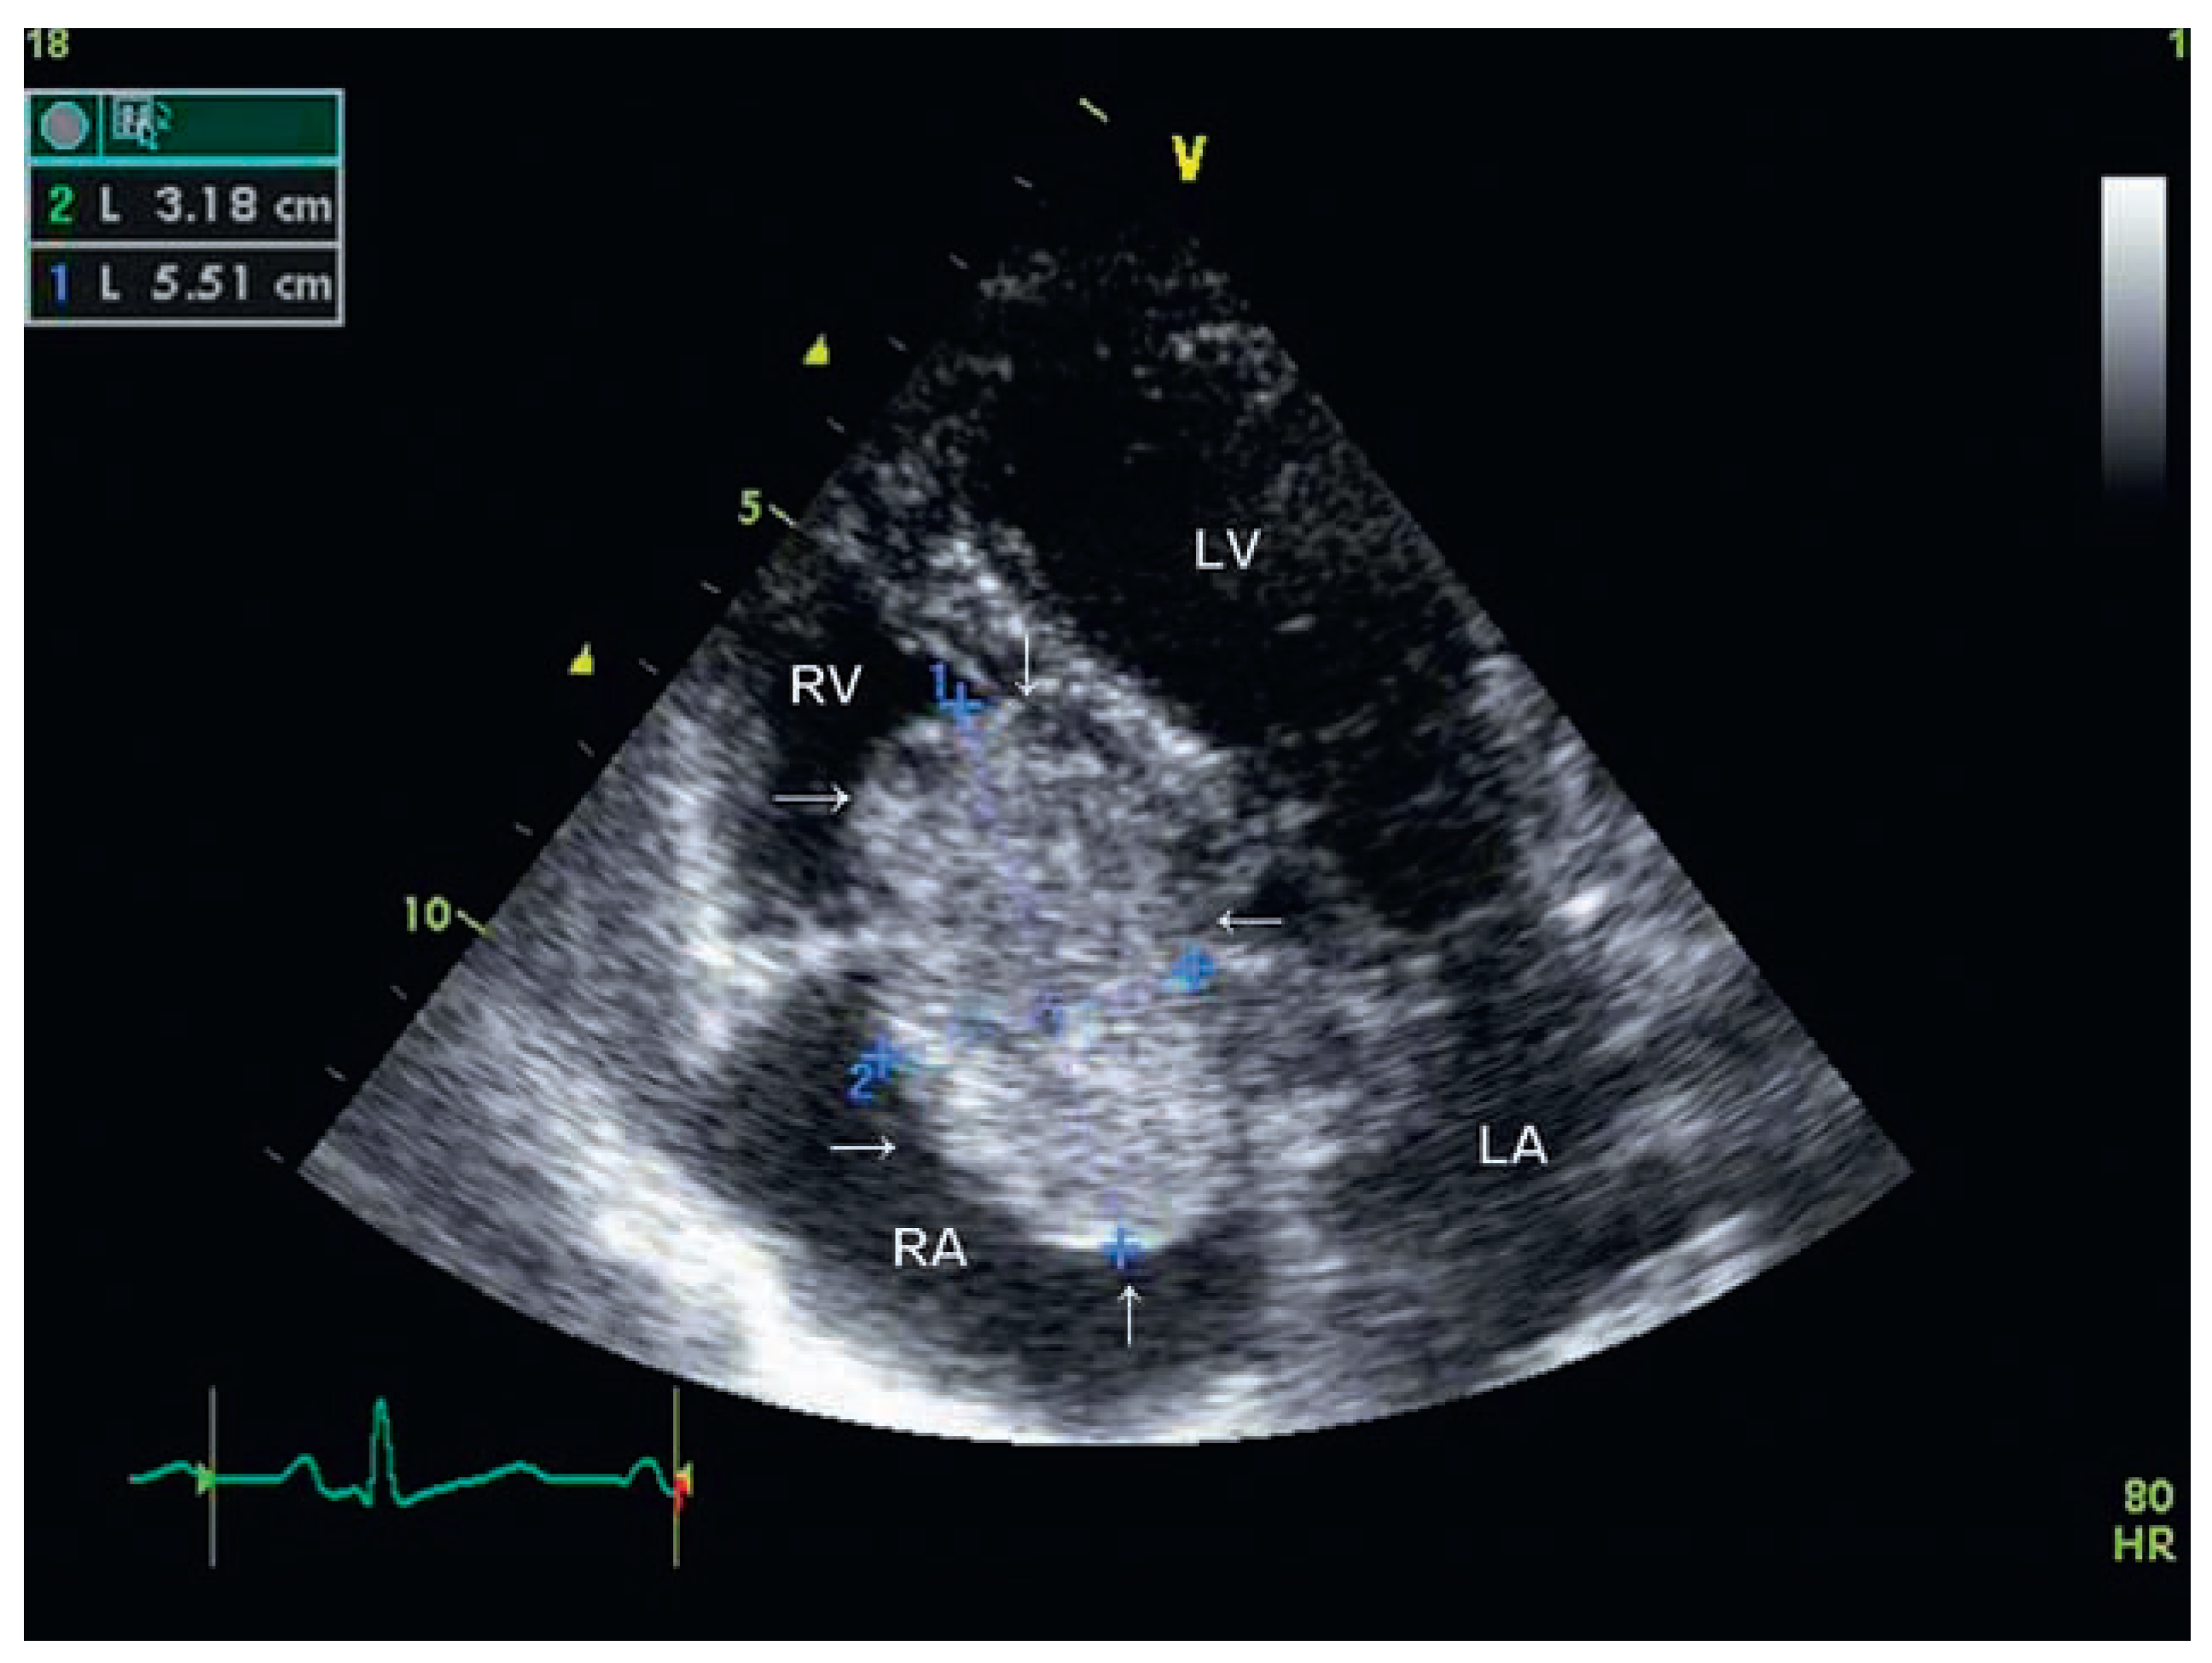

| 1 | ETT apical view showing a pedonculated mass prolapsing into the tricuspid orifice during diastole. |